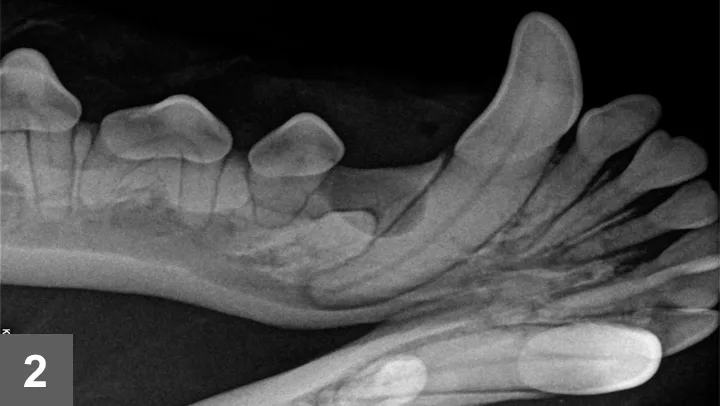

TreatmentAfter right caudal mandibular nerve block and gingival flap elevation, the soft tissue, fluid-filled cyst and unerupted #405 were exposed. The cyst was incised, fluid evacuated, and lining carefully removed by curettage. Tooth #405 was gently elevated, alveolus curetted, radiograph taken, and gingival flap closed with absorbable sutures. A postoperative dental radiograph was also obtained (Figure 4).

Additional DiagnosticsThe entire cyst lining was submitted for histopathologic examination. Histopathologic evaluation confirmed an epithelial lining consistent with a dentigerous cyst.

Figure 4: Postoperative radiograph after surgery to remove dentigerous cyst and tooth #405